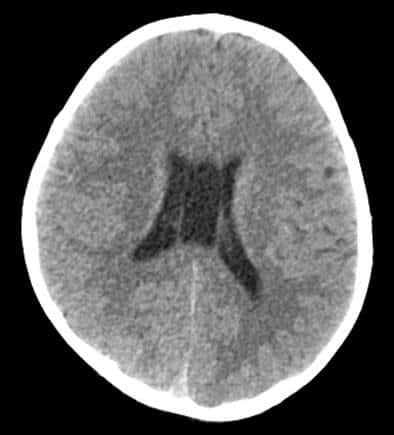

Xuất hiện nang vách ở não, có nguy hiểm không?

Chào BS, Em 20 tuổi, vừa qua em hay đau đầu chóng mặt nên đi khám bác sĩ cho chụp cắt lớp kết luận có nang vách ở não, xin hỏi nang này là gì và có nguy hiểm không? Nhờ bác sĩ tư vấn giúp em ạ. (Thiên Hà – Thủ Đức)